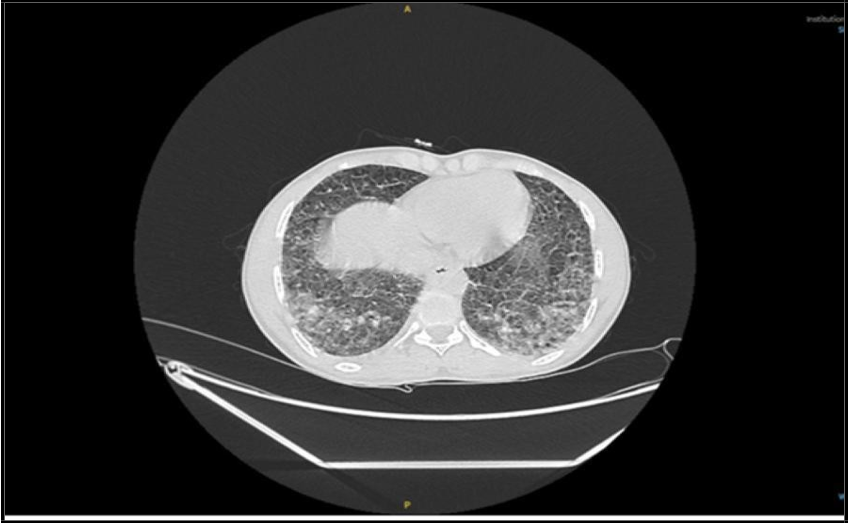

After three weeks on the four-drug anti- tuberculous regimen, the patient deteriorated, initially presenting with a mild, itchy maculopapular rash, followed by the onset of nausea and pyrexia. He was treated symptomatically, and pyrazinamide was discontinued as it was suspected to be the cause of the rash. Although his initial symptoms began to improve following the discontinuation of pyrazinamide, within a few days the patient deteriorated further— developing shortness of breath, elevated inflammatory markers (CRP increased to 87 mg/L, Procalcitonin to 0.6 ng/mL), and a one-fold elevation in transaminase liver enzymes. A requested sputum culture failed to identify any superadded bacterial or fungal pathogens. High- resolution CT chest done and showed a progressive course.

(“29 Dec. 2024”) CT showed Focal patchy consolidative opacity noted in right upper lobe with multiple poorly defined linear and reticulo- nodular opacities in bilateral lower lobes.

Due to the progression of symptoms— including worsening shortness of breath, a drop in SpO₂, and a generalized skin rash— the patient was transferred to the ICU and initiated on oxygen support. A repeat chest X-ray revealed features consistent with Acute Respiratory Distress Syndrome (ARDS). This was accompanied by a progressive rise in inflammatory markers (CRP increased to 154 mg/L, procalcitonin to 15 ng/mL), and a five-fold elevation in liver transaminase levels. Viral screening tests for Measles, Epstein-Barr Virus (EBV), Cytomegalovirus (CMV), and Rubella were requested and all returned negative. The Electrocardiogram (ECG) was unremarkable, and echocardiography revealed normal wall motion and thickness, with a preserved ejection fraction of 55%. However, Pro-BNP was markedly elevated at 3000 pg/mL. Following evaluation by the infectious disease consultant, first-line anti- tuberculous medications were discontinued, and second-line anti-TB therapy was initiated along with a course of corticosteroids.

(“03 Jan. 2025”), Progressive patchy alveolar infiltrate, moderate Rt side effusion.